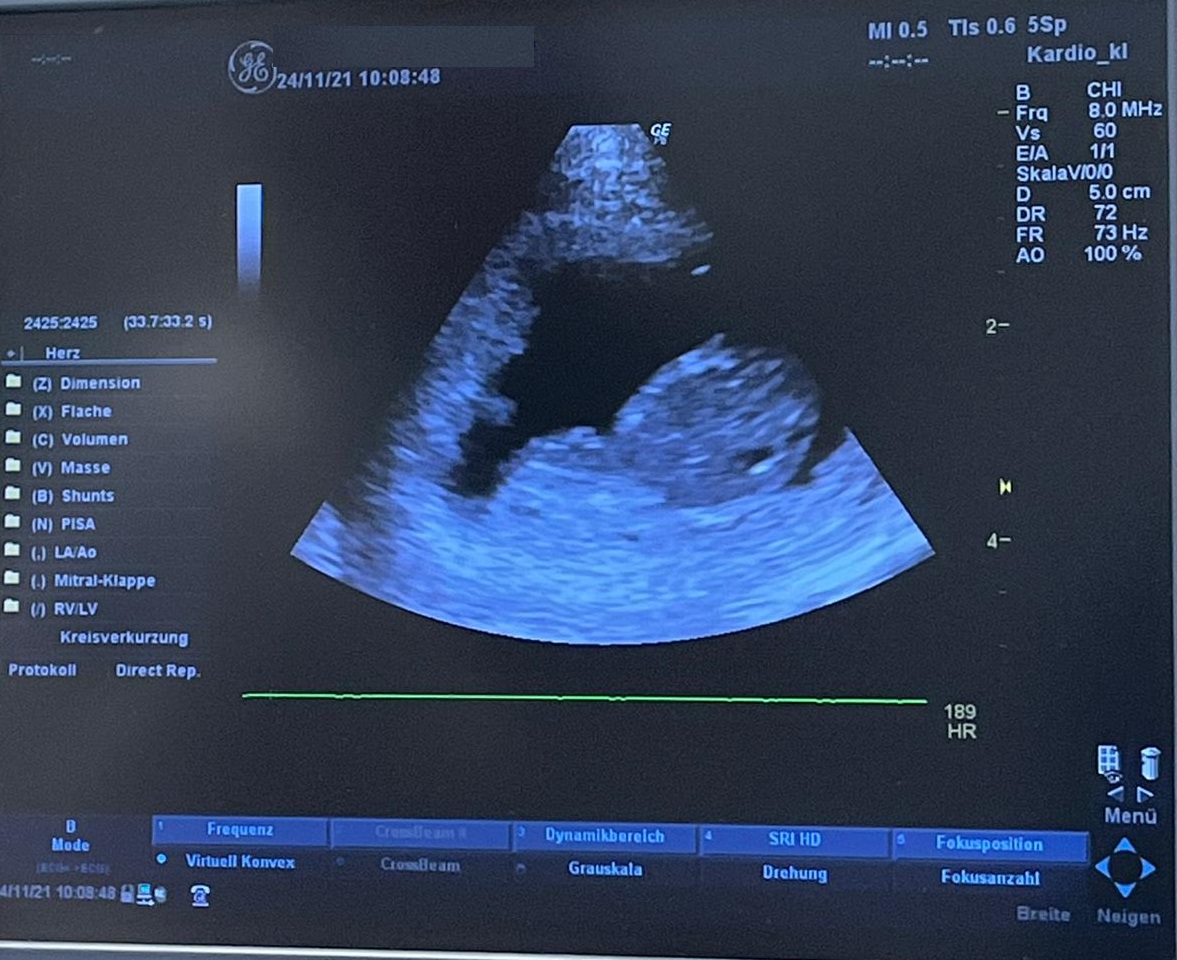

Ultraschallbild, 24.11.2021